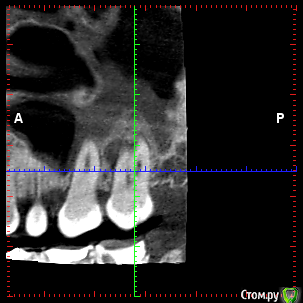

rezo47 Опубликовано 24 сентября, 2015 Автор Поделиться Опубликовано 24 сентября, 2015 Только пришло КТ, вопросов стало больше((( Ссылка на комментарий

kriokov Опубликовано 24 сентября, 2015 Поделиться Опубликовано 24 сентября, 2015 27 удаляйте Ссылка на комментарий

rezo47 Опубликовано 24 сентября, 2015 Автор Поделиться Опубликовано 24 сентября, 2015 (изменено) 27 удаляйтеДиагноз? Изменено 24 сентября, 2015 пользователем rezo47 Ссылка на комментарий

kladoffka Опубликовано 24 сентября, 2015 Поделиться Опубликовано 24 сентября, 2015 Хр пр 2 Ссылка на комментарий

kriokov Опубликовано 24 сентября, 2015 Поделиться Опубликовано 24 сентября, 2015 Диагноз?что хотите, на выбор(например- "не жилец" ) Ссылка на комментарий

red_butler Опубликовано 24 сентября, 2015 Поделиться Опубликовано 24 сентября, 2015 сначала гистология, потом лечение Ссылка на комментарий